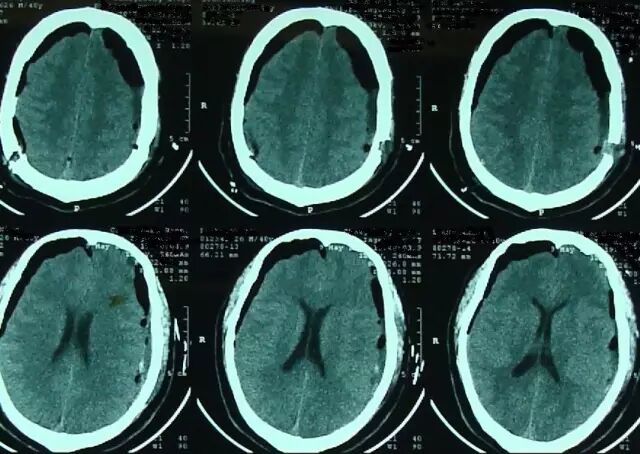

但术后2天再次出现头痛,不能缓解,5月2日复查头颅MRI提示硬膜下血肿术后复发,伴小脑下坠,脑沟及小脑上方仍可见较多脑脊液,四脑室变小,颅内静脉系统扩张明显(箭头所示见横窦扩张)(图3)。

图3. 术后1周(5月2日)复查头颅MRI显示左侧硬膜下血肿术后复发,伴小脑下坠,脑沟及小脑上方仍可见较多脑脊液,四脑室变小,颅内静脉系统扩张明显(箭头所示见横窦扩张)。